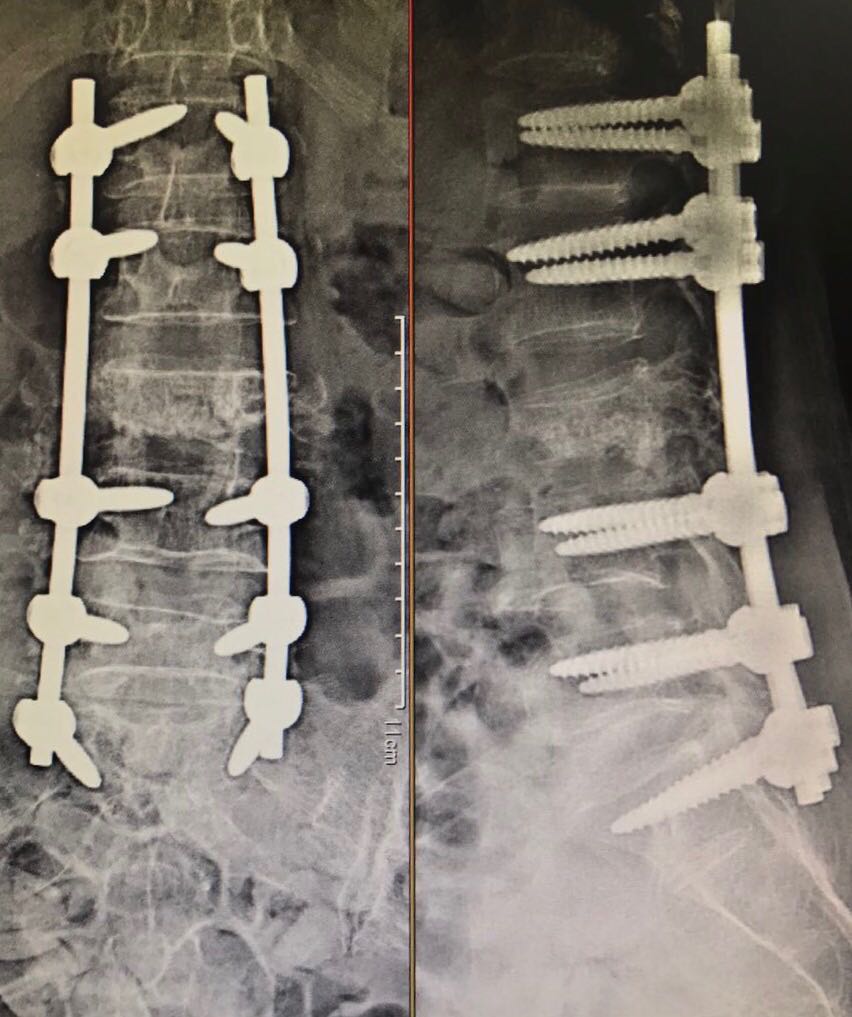

Spine Fracture Fixation

Lumbar fracture fixation is a type of surgery that uses screws or plates to stabilise the vertebrae in the lumbar spine following a fracture.